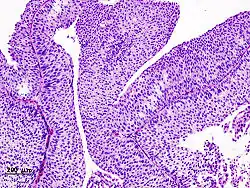

| Histopathology of transitional carcinoma of the urinary bladder. Transurethral biopsy. Hematoxylin and eosin stain. | |

Transitional cell carcinoma, being low-grade to the left, and high-grade to the right. H&E stain -

Papillary transitional cell carcinoma, low grade -

Histopathology of urothelial carcinoma of the urinary bladder, showing a nested pattern of invasion. Transurethral biopsy. H&E stain -

Histopathology of urothelial carcinoma of the urinary bladder. -